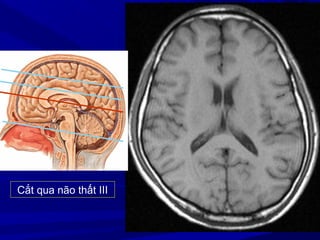

Cắt qua não thất III

Cắt qua nãothất III